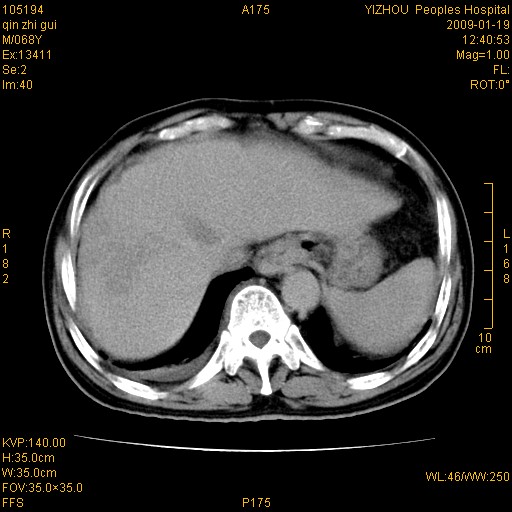

以下是引用随光逐影在2009-1-21 16:11:00的发言:[br]1)考虑肝右叶肝癌并肝静脉及门静脉瘤栓形成。2)肝硬化,少量腹水。3)胆囊炎。4)右侧少量胸腔积液。

病灶外缘凹凸不平,平扫低密度,增强动脉期有强化,门脉早显,静脉期及延期呈延迟强化,结合病史考虑右肝前叶巨块型肝癌可能性大,强化表现不除外胆管细胞癌